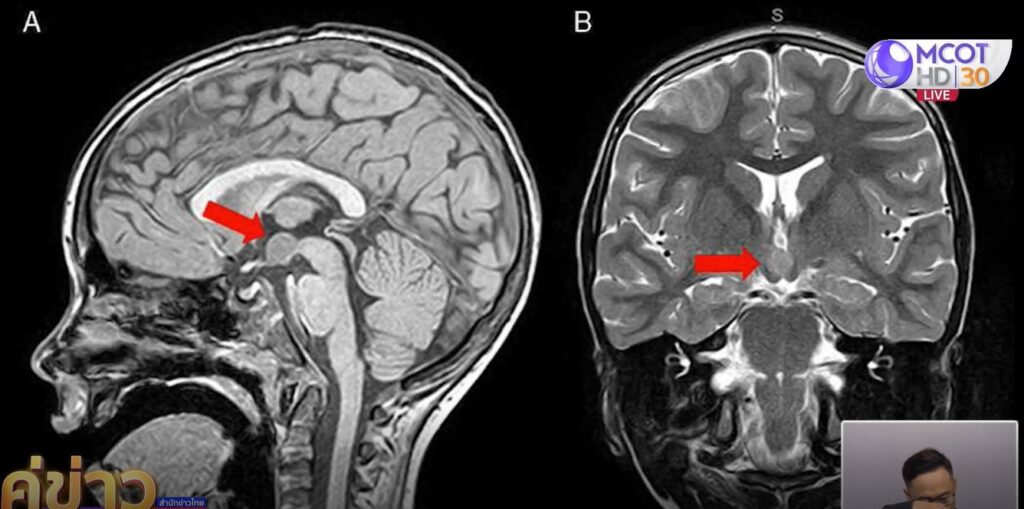

ต่อมาเจ้าของคลิปได้เขียนข้อความเล่าให้ชาวเน็ตฟังว่า ในช่วง 3 เดือนที่ผ่านมา น้องมีอาการหัวเราะไม่มีสาเหตุ ตามมาด้วยชักเกร็งกระตุกทั้งตัว ครั้งแรกที่เห็นคือช็อกมาก บอกใครไม่มีใครเชื่อ คนที่บ้านคิดว่าน้องแกล้งทำเล่น เพราะน้องเป็นคนขี้เล่นมาก แต่คนเป็นแม่ดูออก เลยถ่ายคลิปไปให้คุณหมอดู หมอส่งตรวจคลื่นสมองและตรวจ MRI จึงพบเนื้องอกในสมอง